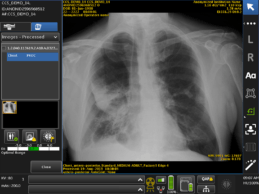

FDA Clears GE Healthcare’s AI Algorithms Embedded on Mobile X-Ray Device

- GE Healthcare awarded Food and Drug Administration’s 510(k) clearance of Critical Care Suite, an industry-first collection of artificial intelligence (AI) algorithms embedded on a mobile X-ray device. - Algorithms help radiologists prioritize critical cases with a suspected pneumothorax – a type of collapsed lung – by immediately flagging critical cases to radiologists for triage, which could drastically cut the average review time from up to eight hours. - Critical Care Suite offers